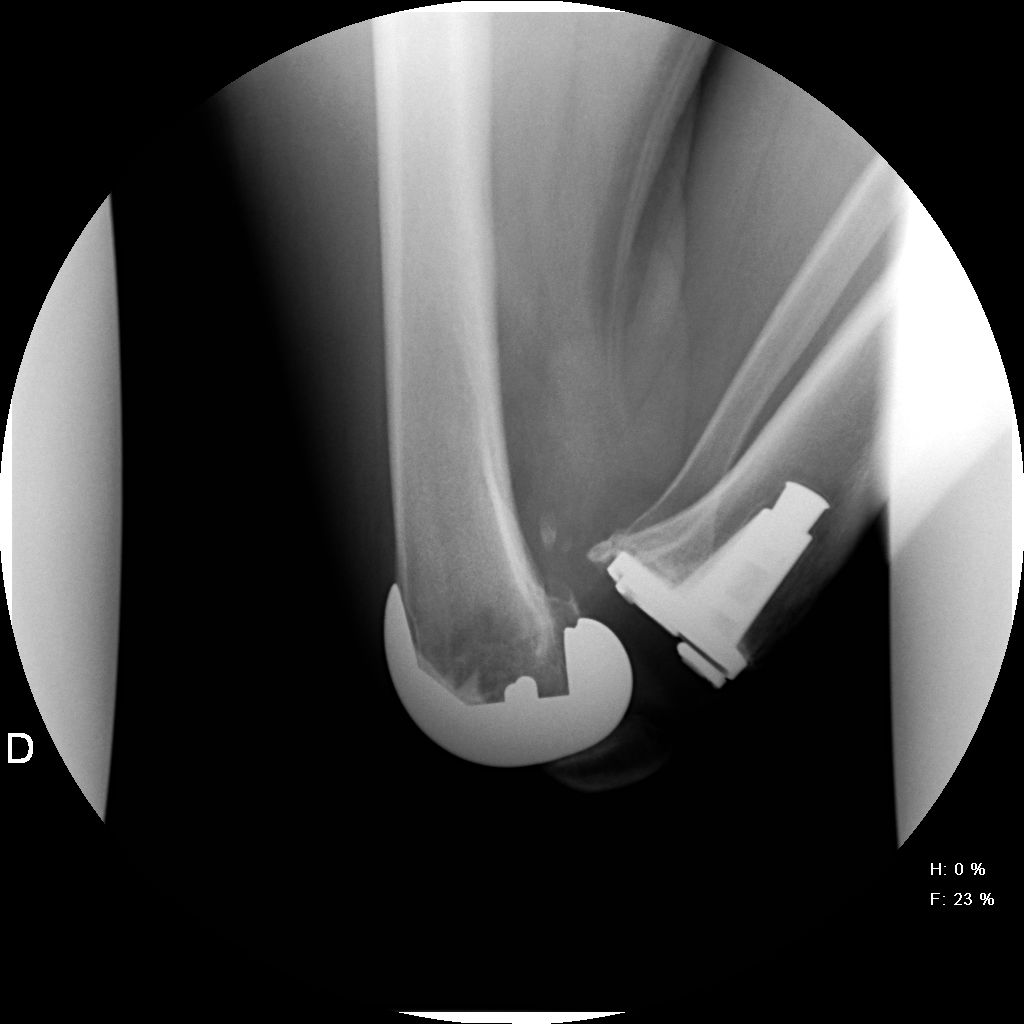

Estudio Comparativo con prótesis total de rodilla de alta flexión. [Comparative study with high-flex total knee arthroplasty.]